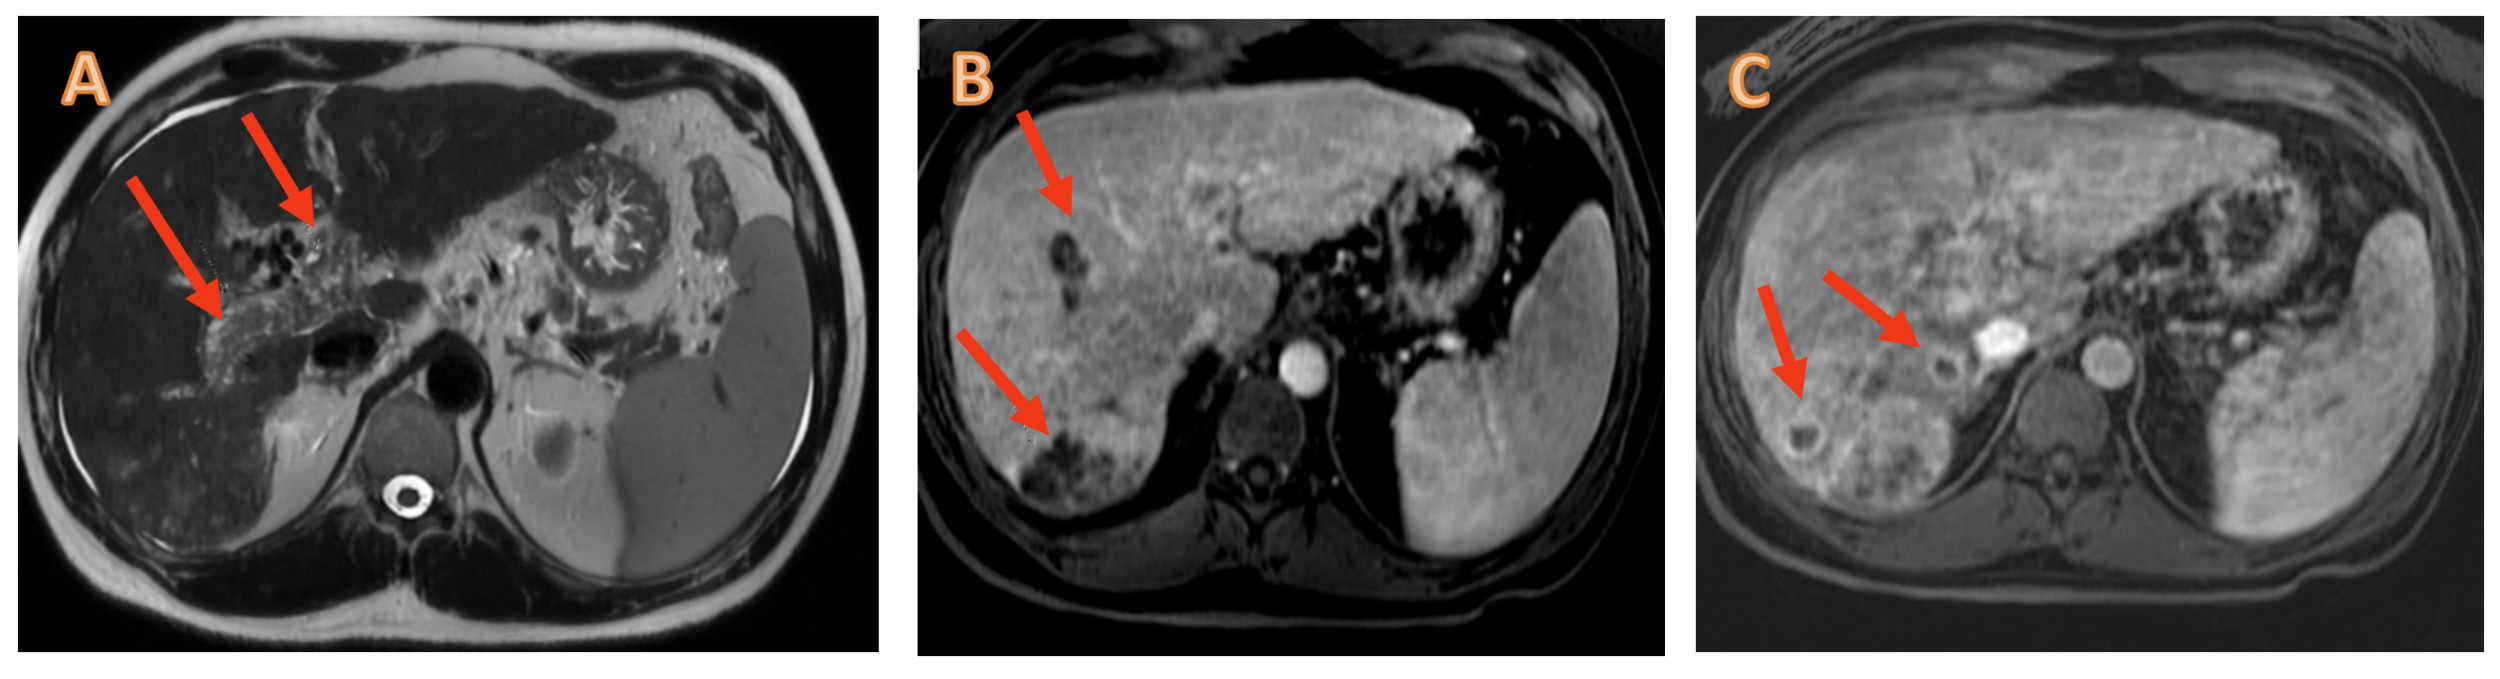

A hepatic magnetic resonance imaging (MRI) scan confirmed the presence of multiple HCC-compatible lesions, complete portal vein thrombosis (PVT) and partial thrombosis of the mesenteric vein (Figure 1).